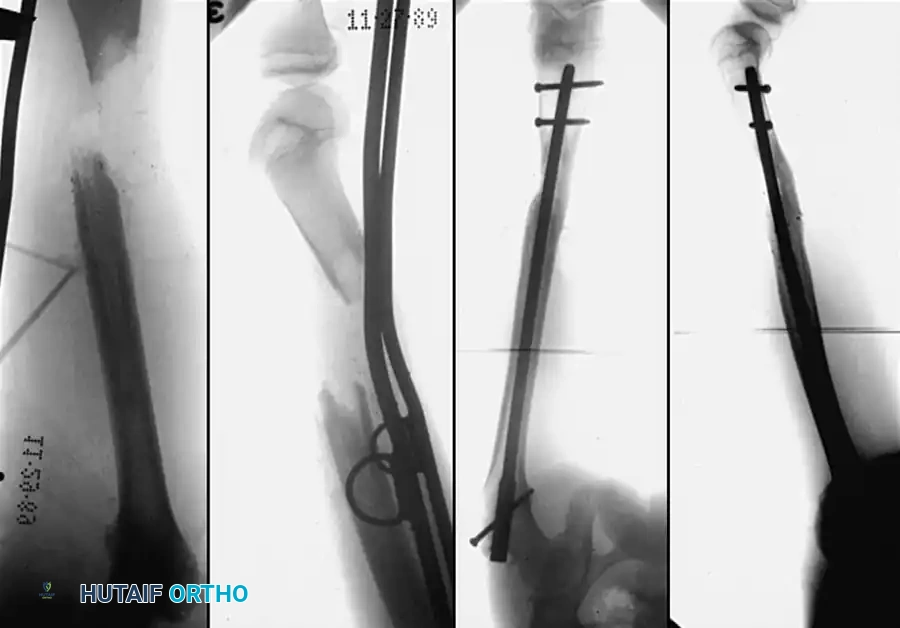

TIBIAL SHAFT NONUNIONS

Many treatment methods have been highly successful in obtaining union of tibial shaft nonunions. Union rates of 72.1% to 87.8% have been reported with closed bone grafting procedures in hypertrophic aseptic nonunions. Internal fixation (intramedullary nailing or plating) has been reported to obtain union in up to 98% of cases, and electrical stimulation in 78.8%.

The surgical technique selected depends heavily on whether the nonunion is hypervascular (hypertrophic) or avascular (atrophic), and whether the alignment of the fragments is satisfactory.

- Hypervascular Nonunions: The bone ends possess excellent biological capacity to unite but lack mechanical stability. In these cases, rigid internal fixation with a compression plate, an intramedullary nail, or a circular external fixator is usually all that is necessary. Supplemental bone grafting is rarely required.

- Avascular Nonunions: The bone ends are sclerotic, necrotic, and lack osteogenic potential. Rigid internal fixation must be supplemented by aggressive decortication of the sclerotic bone ends (shingling) and the application of autogenous bone graft. Weber and Brunner, Müller and Thomas, and Christensen have found these combined methods highly successful.

Judet and Patel reported excellent results treating 290 nonunions of the tibial shaft by internal fixation with plates and screws or intramedullary nails. The fragments were decorticated in all instances, but iliac cancellous grafts were rarely added. Clancey, Winquist, and Hansen treated 48 nonunions of the tibial shaft by Küntscher intramedullary nailing. In 30 cases, the nailing was completely closed, and in only 18 was open tibial osteotomy necessary to realign the fracture. Bone grafting was not used, and all but two nonunions healed.

In the past, most nonunions of the tibial shaft were treated with a massive cortical onlay bone graft with satisfactory results. While this method is rarely used today due to the advent of locked intramedullary nailing and locking plate technology, it remains a historically significant technique that is occasionally useful for nonunions in the extreme proximal or distal fourth of the tibia, or when dealing with severely sclerotic fragments where intramedullary instrumentation is impossible.

Fig. 56-20 A, Nonunion after osteotomy. Failure to produce union by sliding inlay graft; fibula is intact. B, Four years after application of dual onlay grafts and osteotomy of fibula.

Fig. 56-21 A, Oblique comminuted fracture of proximal third of tibia. B, Satisfactory restoration. C, Fracture of shaft failed to unite; treated by dual onlay graft.